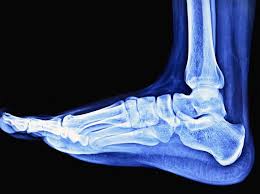

발등이 붓는 이유와 근본 원인, 해결책

발등이 붓는 이유는 많은 사람들이 겪는 일반적인 증상입니다. 그러나 이와 같은 증상은 단순한 피로에서 비롯된 것이 아닐 수 있습니다. 발등이 붓는 이유는 혈류 장애와 염증, 외부 압박 등이 복합적으로 작용하여 발생합니다. 특히, 아침에 일어났을 때 발등이 붓는 경우에는 더욱 신경을 써야 합니다. 오늘은 발등이 붓는 이유에 대해 자세히 알아보고, 그 해결책에 대해서도 논의해보겠습니다.